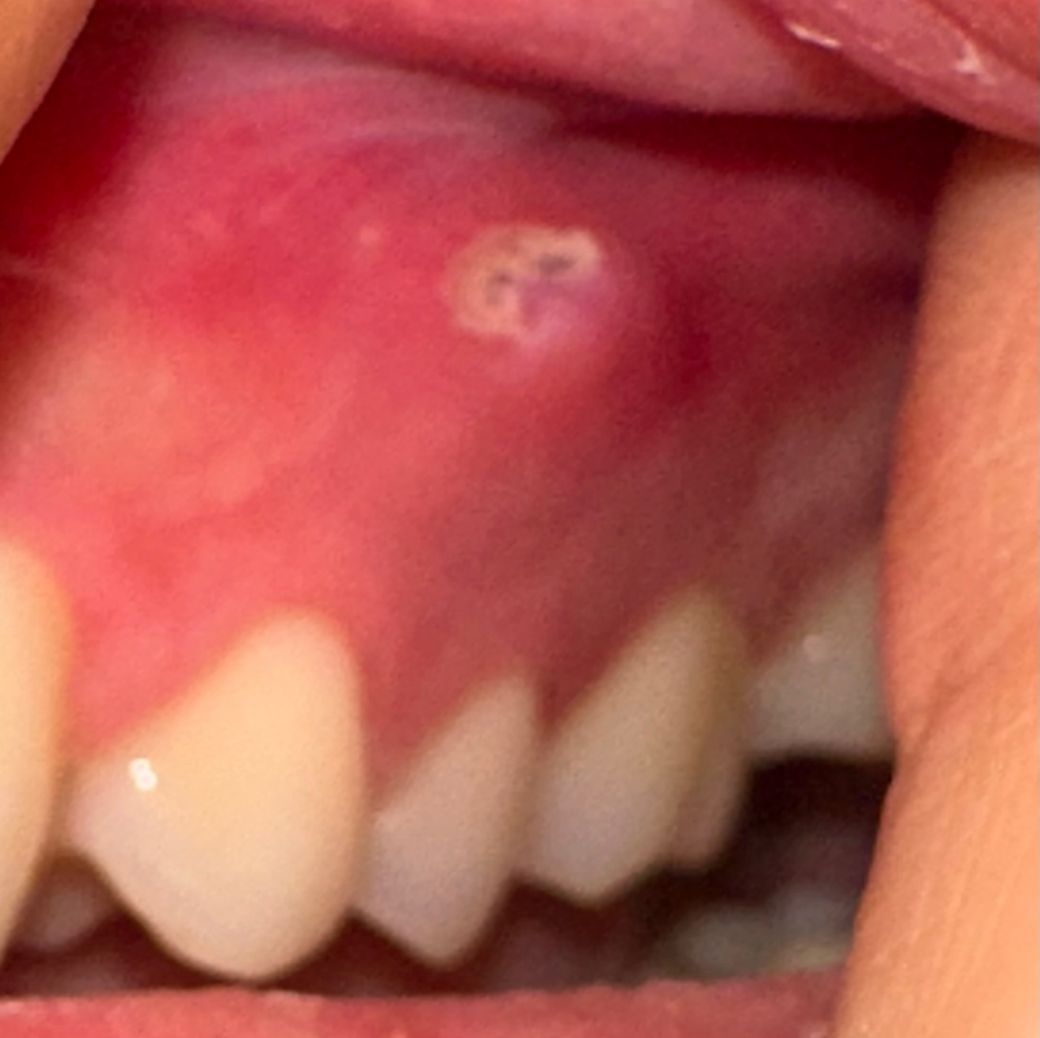

잇몸에 있는 이거 구내염이 맞는건가요?

잇몸에 뭔가 구내염 느낌이 들어서 알보칠을 바르고 어떤지 한번 거울로 봤는데 약간 검은 뭔가 있어서 구내염이 맞는지 잘 모르겠어요. 일단 바른 뒤에 최대한 잘 보이게 찍어봤는데 잇몸이 곪은건지 그냥 구내염인지 확인바랍니다.

• 1번 째 사진

현재 잇몸 상태를 보아서는 구내염이 아닌 치아 뿌리에 문제가 생겨 나타난 염증일 가능성이 큽니다. 잇몸 자체가 부어 있는 것으로 보아 sinus tract이 생겨서 치아 뿌리에 있는 염증이 바깥으로 나오면서 생긴 흔적으로 보여집니다. 정확한 판단을 위해서는 x-ray 등의 촬영이 필요할 것으로 보입니다. 너무 늦지 않게 치과 방문을 권해드립니다.

해당 부위 자극에 의해 발생한 궤양으로 추정되며 구내염의 일종으로 보입니다. 경과관찰 후 증상 개선 없을 시에는 정확한 평가 위해 구강악안면외과 또는 구강 내과 내원하시기를 바랍니다.